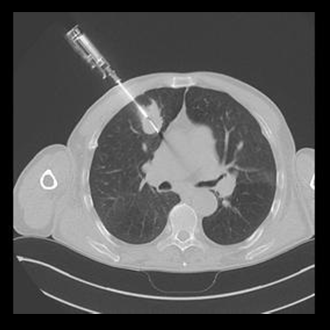

BIOPSY

Biopsy and Drainage

We at Gokul Diagnostic and Scan Centre provide facilities for various radiological interventions under the guidance of CT Scan, XrayFluroscopy and Ultrasonography.

As we have availability of various modalities we choose from CT or Sonography guidance whichever is best suited for the patient under given clinical scenario.

We have a team of dedicated radiologists who are highly trained in doing imaging based interventions.

We have excellent success rates with patient safety being our priority.

We Perform :

1. CT/USG guided biopsies.

2. CT/USG guided drainages.

3. FNAC